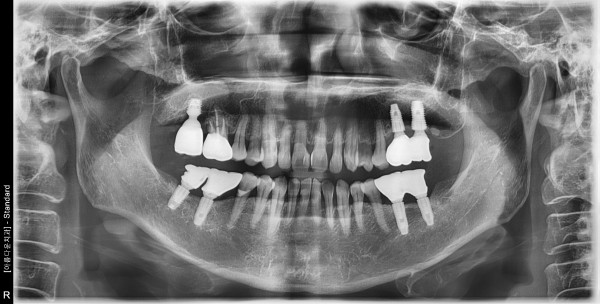

65세 여자 상악 우측 구치부 발치, 치조골이식술 후 임플란트 식립